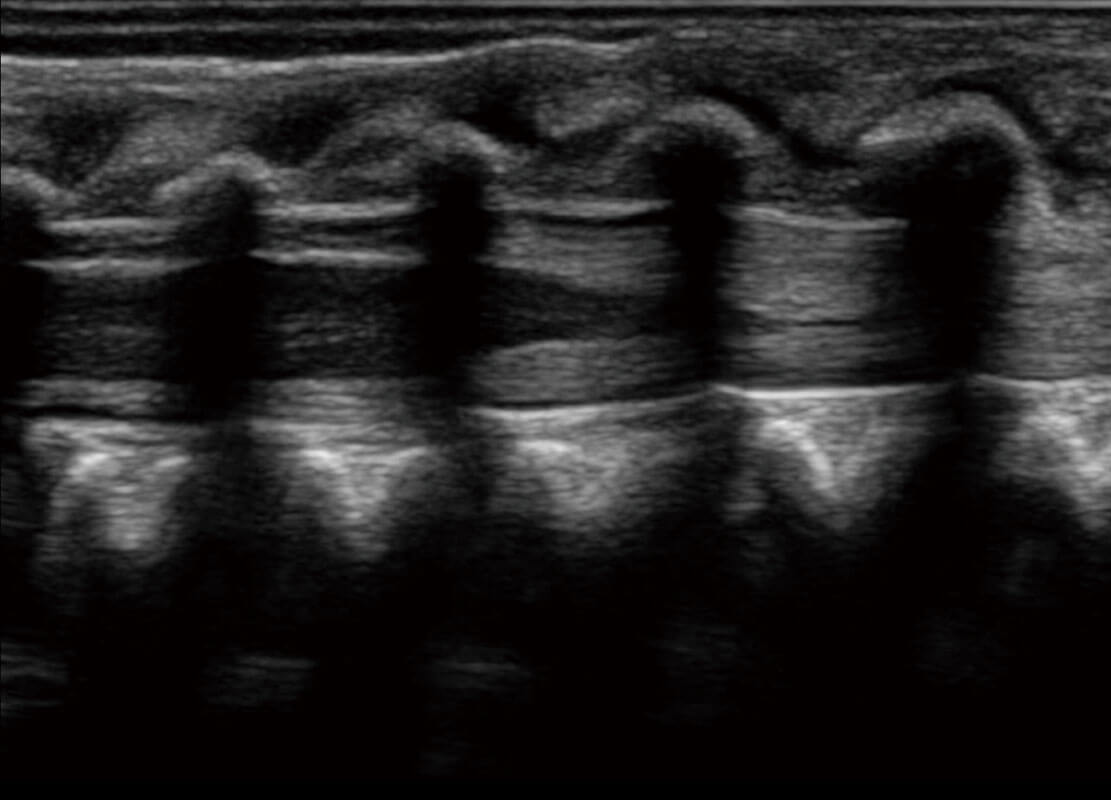

乳腺超声 / 新生儿

P60搭载宽频带线阵探头、宽景成像、弹性成像技术,为您提供乳腺应用方案。P60支持高频相控阵探头、线阵探头、腹部高频探头、腹部微凸探头等,丰富的探头群搭载敏感的彩色血流成像,适用于新生儿多种脏器检测要求,满足新生儿筛查需求。

• 新生儿脊髓圆锥